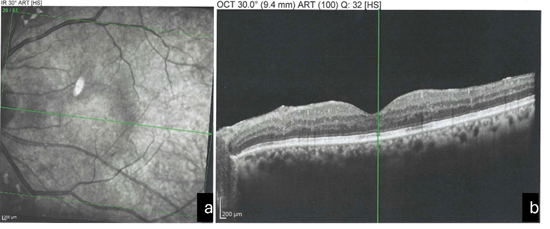

Transient elevation of IOP was noted in a small number of patients during the immediate post-procedure period, which was successfully managed with topical IOP-lowering medications. No cases of retinal detachment, persistent uveitis, or visually significant IOL pitting were observed during the follow-up period. Figure 2a and 2b show the OCT images after treatment.

Figure 2a and 2b: OCT Image after Treatment.